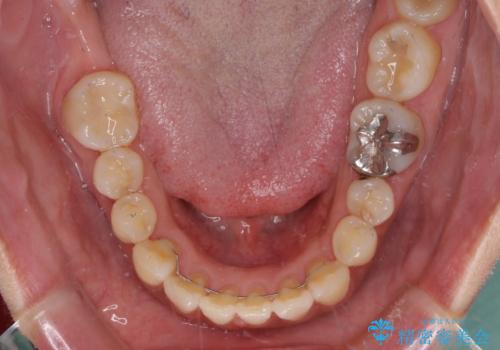

軽度な歯列不正 インビザライン・ライトによる矯正治療

インビザライン・ライトは、製作できるアライナーの枚数に制限があるため、移動可能な量に限りがあります。

一方で、半年から1年程度で治療を終えることができるため、軽度の歯列不正の患者様には大変お勧めです。